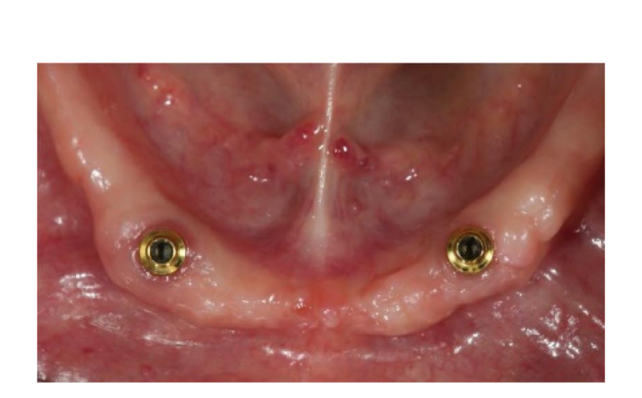

Dopo l'intervento, ai pazienti è stato consigliato di evitare qualsiasi trauma nel sito chirurgico, comprese le procedure di spazzolamento. È stata prescritta una dieta fredda e morbida post-chirurgica. Dopo l'intervento, ai fumatori è stato consigliato di astenersi dal fumo per due settimane. Sono state fornite istruzioni dettagliate per l'igiene orale, inclusa la raccomandazione di sciacquare tre volte al giorno con clorexidina allo 0,12%. Sono stati prescritti analgesici, come 600 mg di ibuprofene o alternative simili, secondo necessità. I punti di sutura sono stati tipicamente rimossi entro un periodo di dieci a quattordici giorni. Secondo un flusso di lavoro precedentemente riportato, le procedure protesiche sono iniziate otto settimane dopo l'inserimento degli impianti. Secondo un protocollo di carico precoce, una nuova dentiera rimovibile completa rinforzata in metallo è stata consegnata in entrambi i gruppi entro quattro settimane dopo l'inserimento degli impianti. Dopo due o tre giorni, gli abutment di guarigione sono stati svitati e gli attacchi sono stati collegati a lato della poltrona alla nuova protesi rimovibile. I pazienti sono stati randomizzati per ricevere attacchi OT Equator® (Rhein’83, Bologna, Italia) nel gruppo di test o attacchi Locator (Zest Anchors LLC) nel gruppo di controllo. I sistemi di attacco randomizzati sono stati posizionati e serrati secondo le istruzioni del produttore. Nel gruppo di test (Figure 1–5), dopo la guarigione gengivale, i più recenti attacchi OT Equator® a basso profilo sono stati avvitati sugli impianti utilizzando il cacciavite quadrato OT Equator®, con un intervallo di coppia di 22–25 Ncm. Le altezze dei manicotti variavano da 0,5 a 7,0 mm, a seconda delle dimensioni della zona di transizione di ciascun impianto, facilmente misurabili utilizzando il misuratore di altezza del manicotto millimetrico a codifica colore (Rhein’83, Bologna, Italia) dopo la rimozione dell'abutment di guarigione. Successivamente, è stato preparato lo spazio necessario per accettare la gabbia in acciaio della sede femminile nella superficie di adattamento della dentiera rimovibile completa mandibolare. Dischi protettivi in silicone (Rhein’83, Bologna, Italia) sono stati posizionati sopra gli attacchi OT Equator®. Cappucci di ritenzione extra-morbidi (giallo, 600 g) sono stati inizialmente inseriti nella sede femminile in acciaio, attaccati a OT Equator®, e infine fissati alla dentiera utilizzando resina acrilica autoindurente. Allo stesso tempo, il paziente ha tenuto le dentiere in occlusione, direttamente a lato della poltrona. Dopo la completa polimerizzazione, la dentiera è stata prelevata e i dischi in silicone sono stati rimossi. L'eccesso di acrilico è stato rifilato e la dentiera è stata rifinita e lucidata. Un mese dopo la consegna delle protesi, i cappucci di ritenzione gialli sono stati sostituiti con un tipo più robusto (rosa, 1200 g).